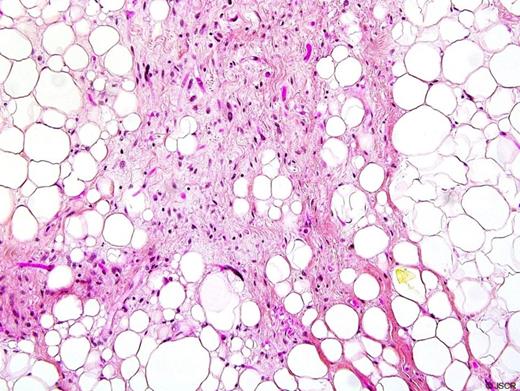

On gross pathologic examination, the mass measured 13 x 9 x 3 cm and weighed 297 grams. Cut section revealed an indurated calcified mass with a lobulated aspect and a whitish coloration. The lesion was well circumscribed but not encapsulated. Microscopically, the tumour was composed of adipocytes of varying sizes including univacuolated and multivacuolated lipoblasts with a large hyperchromatic nucleus (Figure 2). Several fibrous septa containing atypical stromal cells with hyperchromasia were also noted. Immunohistochemistry revealed diffuse and intense tracer uptake for Vimentine, light to moderate uptake of CD34, and a tracer uptake of several fusiform cells and adipose cells with the protein S-100. Based on the above morphological and immunohistochemical characteristics, the definitive diagnostic was consistent with a well-differentiated liposarcoma (atypical lipomatous tumour). There were no features of dedifferentiation.

Histological examination of the mass showing adipocytes of varying sizes including univacuolated and multivacuolated lipoblasts with a large hyperchromatic nucleus.